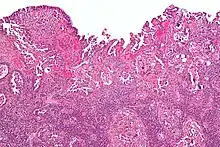

| Histology H&E of uterine serous papillary carcinoma. H&E stain. | |

Histopathologically, uterine serous carcinomas is typically characterized by (1) nipple-shaped structures (papillae) with fibrovascular cores (2) marked nuclear atypia (irregularities in the nuclear membrane, enlarged nuclear size), (3) psammoma bodies and (4) cilia.